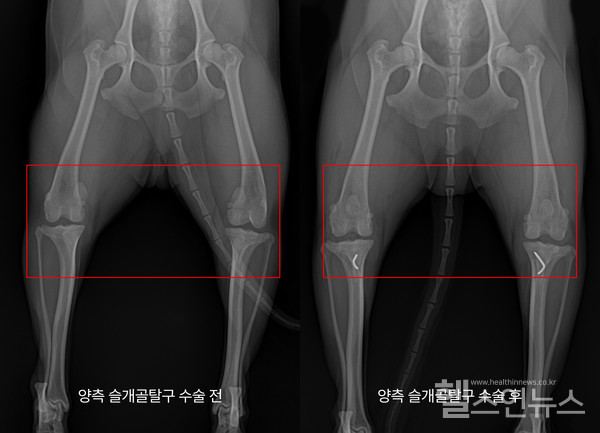

슬개골탈구로 인해 동물병원에 내원하면 촉진, 방사선 촬영을 통해 정확하게 슬개골탈구 단계를 파악한다. 슬개골탈구가 심한 아이들은 방사선 사진만 보아도 슬개골이 외측으로 많이 빠져 있는 것을 확인할 수 있다. 대부분 활차구 성형술과 경골조면 이식술을 통해 교정한다. 활차구 성형술은 얕은 활차구를 깊게 성형해 주는 방법으로 안정적으로 슬개골이 도르래운동을 할 수 있게 도와준다. 경골조면 이식술은 돌아간 경골(종아리뼈)에서 슬개골 인대와 연결되어 있는 경골 조면을 잘라내 활차구와 일직선이 되게 고정해 주는 수술이다.